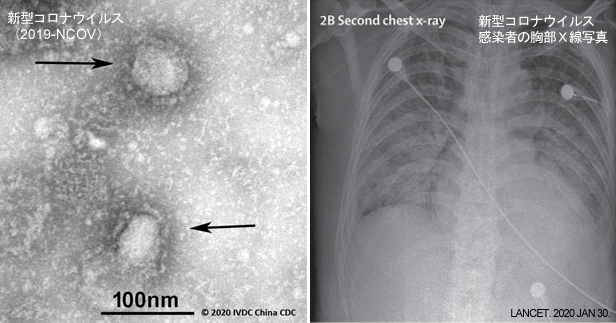

新型コロナウイルスと霊芝

2019年12月に中国で発生した新型コロナウイルス「covid-19」は、中国国内のみで1665人の死者を出し、感染者数は6万8500人まで増加した。(2月16日时点)2003年に流… 2020-02-16 17:54